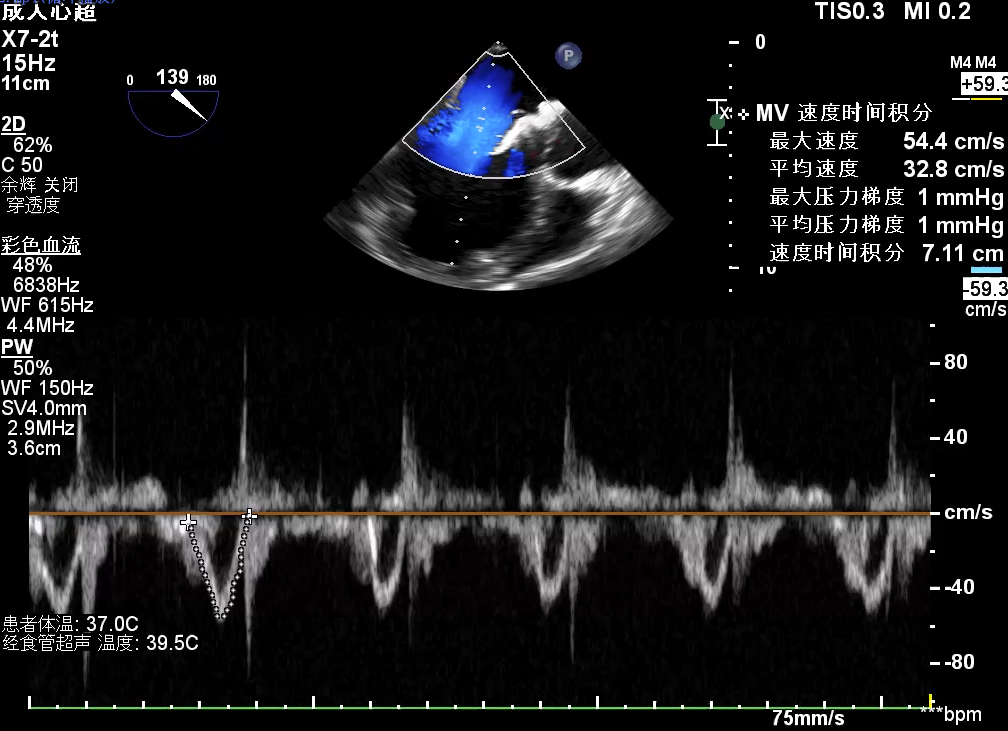

手术采用左侧第六肋间微创5cm切口心尖入路,在超声引导下,清晰识别MitraFix®输送系统准确跨瓣,并将人工瓣膜准确释放于二尖瓣瓣环,瓣膜释放后支架贴合牢固,术后无反流,二尖瓣前向血流通畅、跨瓣压差1mmHg,左心室流出道通畅,流出道血流速度为1 m/s. 后顺利撤出输送系统,关闭心尖切口,手术顺利结束。